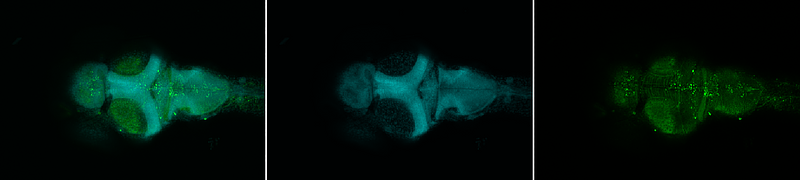

Individuals with autism spectrum disorder (ASD) have a greater prevalence of deficits in social interactions and repetitive behaviours, which are influenced by hereditary and environmental factors. How environmental factors influence genetically predisposed individuals remains unknown. Here, we provide new evidence of the interplay between social behaviour and environmental influences, by manipulating perceived safety and threat levels in ube3a mutant zebrafish, a mutation that is linked to Angelman syndrome and ASD. Mutant fish demonstrated abnormal social behaviour in an aversive custom-made Styrofoam container, whereas these abnormalities ameliorated in a preferred Plexiglass setting. Our findings were further supported by elevated anxiety levels in the mutants when they performed conventional anxiety-related tests, such as the light‒dark test (LDT) and the novel tank diving test (NTT). Additionally, neural activity mapping using c-Fos in situ hybridization revealed differences in activation patterns in the brains of the mutants. Importantly, we performed an overrepresentation analysis (ORA) using RNA sequencing data from ube3a mutants and integrating datasets from human diseases. We identified the upregulation of vision- and comorbidity-related genes in ube3a mutants and alterations in sensory pathways, highlighting that abnormal processing of visual information is the cause of increased anxiety levels, resulting in decreased social interaction in a stressful Styrofoam environment. Our findings underscore the crucial impact of environmental factors on social behaviour and indicate that therapeutic options for ASD that focus on adjusting environmental contexts to modify perceived stimuli may ameliorate ASD-like behaviours.